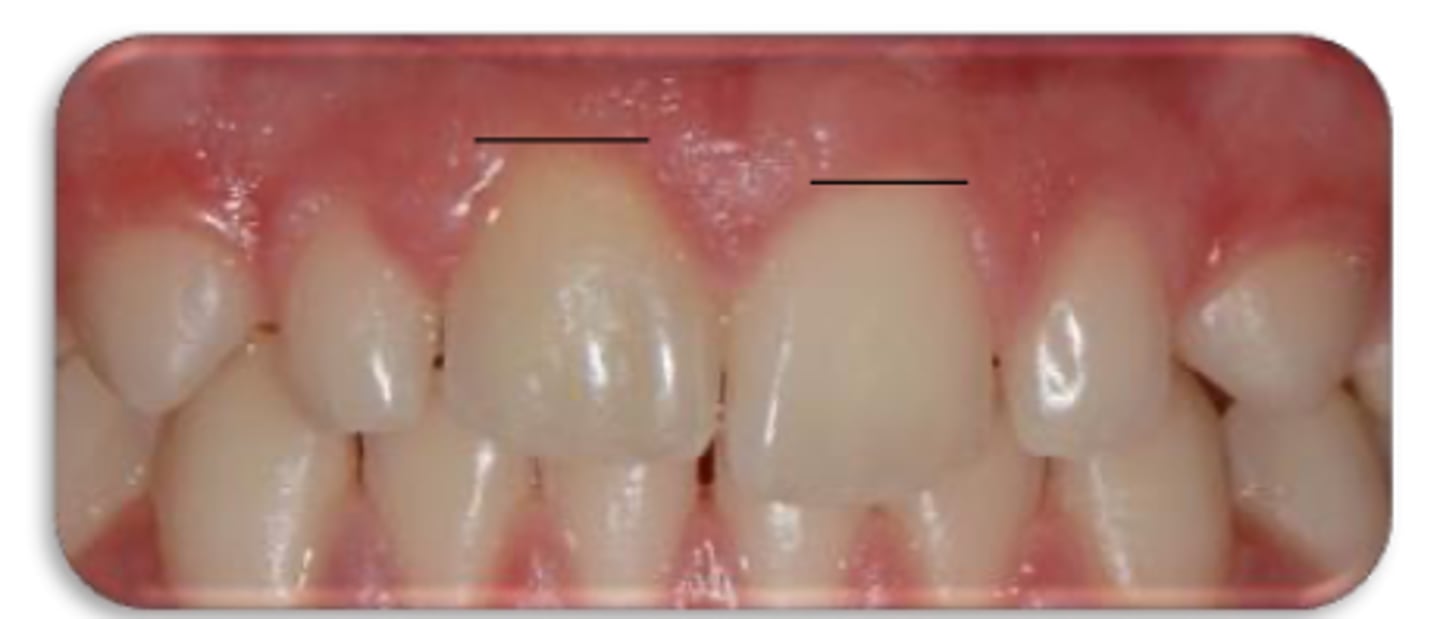

External cervical resorption (Invasive Cervical Resorption)

ID the type of resorption:

- Often asymptomatic until late stages, and may be misdiagnosed as caries

- Possible pink spot in the cervical aspect of the tooth, near gingival margin

- Often hemorrhagic on probing

- Feels hard and scratchy when probed (unlike subgingival caries which feels sticky)

A patient presents asymptomatic with a pink spot in the cervical aspect of the tooth, near the gingival margin. Upon probing, the pocket is hemorrhagic and feels hard/scratchy. What is the most likely diagnosis?

- Usually an incidental radiographic finding, especially for less advanced lesions

- Variable appearances; may be a well-defined or irregular radiolucency around the cervical aspect of the tooth

- A portal of entry is always present in the cervical region of the tooth

- The chamber/canal outline is often visible as the innermost layer of predentin around the chamber is not resorbed

Patient presents with these radiographic findings, what type of resorption?

- Incidental finding

- Radiolucency around cervical aspect of tooth

- Portal of entry present in cervical region

- Chamber/canal outline is visible